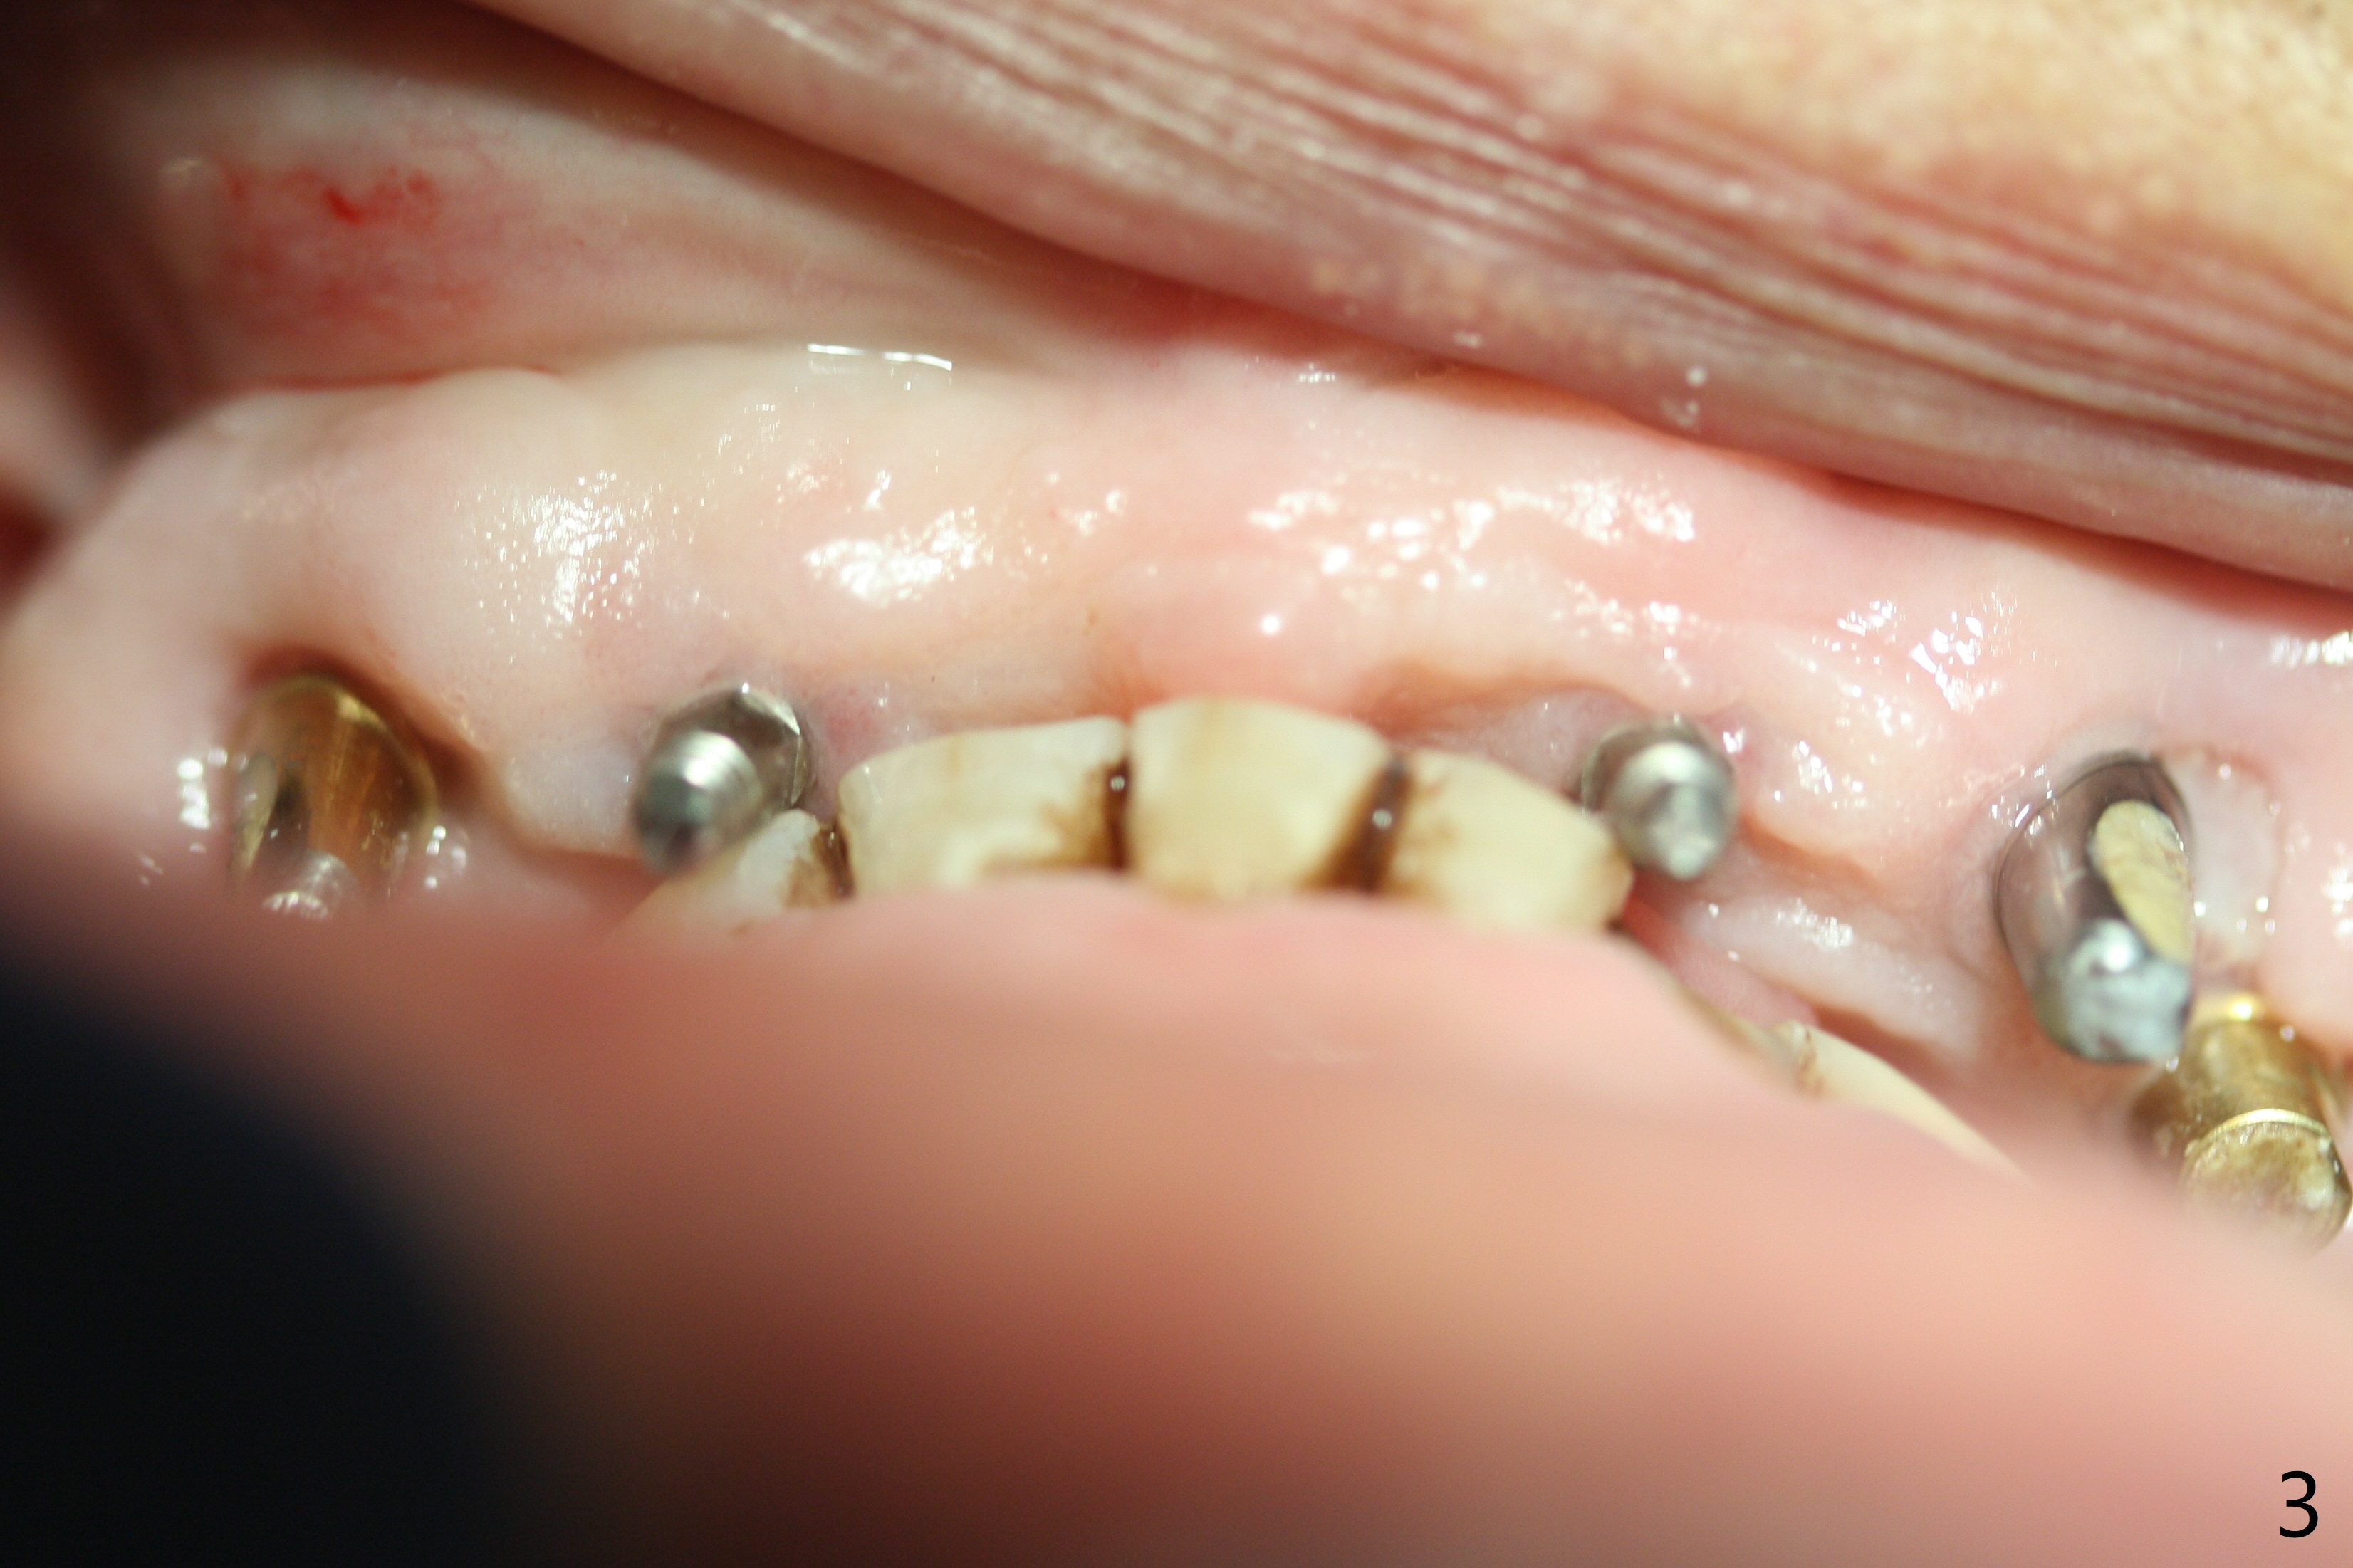

To have enough clearance for the splinted provisional at #6-12 (Fig.1 *), composite has been placed in the posterior teeth (bilateral, *, Fig.2). When the composite is removed, there is no clearance between the implants/abutments of #7 or 10 (Fig.3). Incision is made with removal of the 1-piece implant at #7; there is enough bone to move the osteotomy buccal (Fig.4 arrowhead). When the same implant is placed buccal (Fig.5), there is sufficient clearance for restoration (Fig.6 *), while there is still enough buccal bone left (Fig.7). When the patient returns 5.5 (for #7 and 10)/6.5 (#6,11,12) months postop, his chief complaint is tenderness lingual to #11. In fact, the abutment screw is loose at #11, while the implant at #10 has mobility (Fig.8), which is related to loss of the posterior stops (*) due to wear. There is slight bone loss mesial to #10 implant 5.5 months postop (Fig.10, as compared Fig.9). CBCT taken 5.5/6.5 months postop shows no bone loss (Fig.11-15). The 3x14 mm 1-piece implant at #10 is mobile 9 months postop and is removed and replaced by a 3.5x13 mm 2-piece one with slightly buccal osteotomy (Fig.16). PAs are taken prior to impression (Fig.17,18). The abutment at #12 is loose (<). More composite needs to be added to the occlusal surface of the upper posterior teeth. Finally the patient agrees to have crowns for the upper posterior teeth.